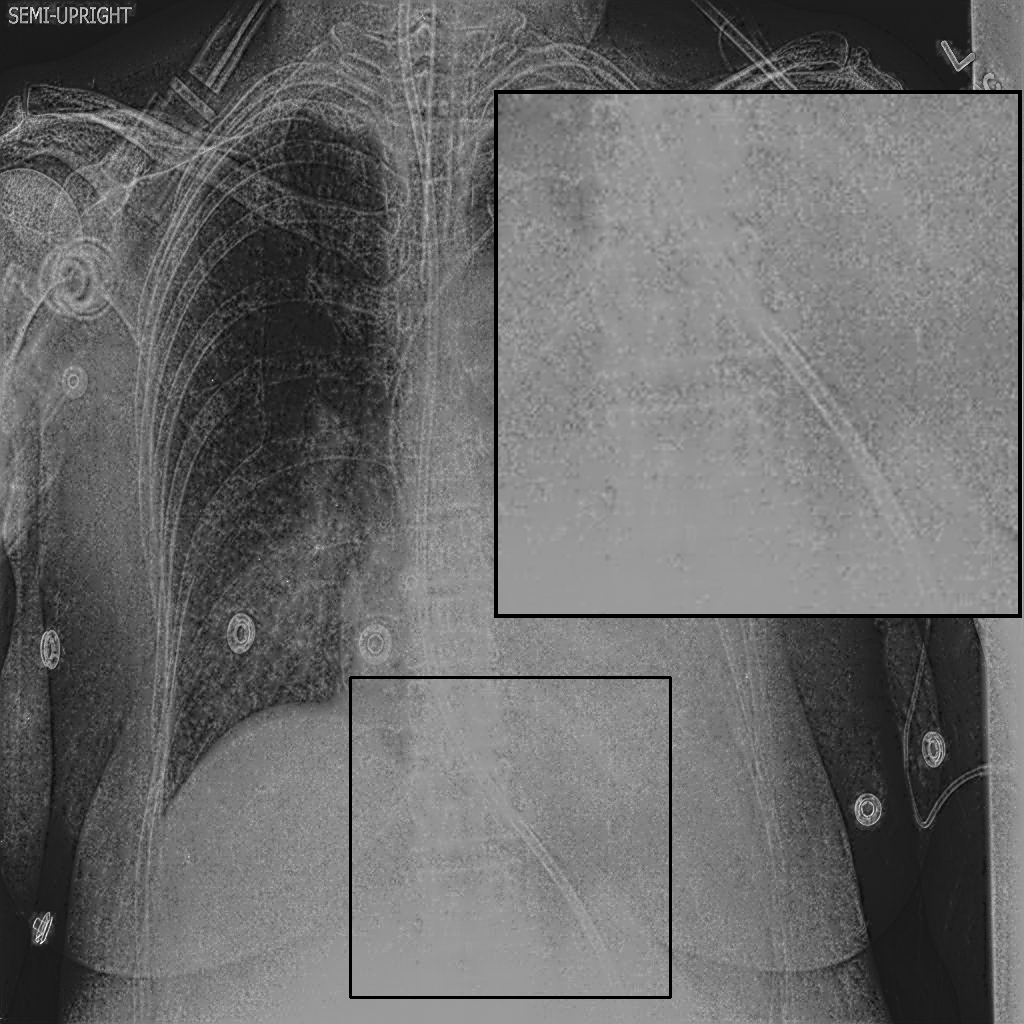

Fig. 3 shows image samples from the above datasets.

Figure 3: Image diversity across four datasets: (a) JSRT, (b) Montgomery County X-ray, (c) NIH ChestX-ray14, and (d) CheXpert